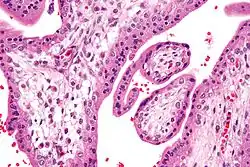

Micrograph showing chorionic villi. Very high magnification. H&E stain. -